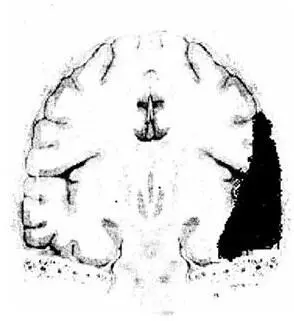

Высокая прочность сращения твердой мозговой оболочки в области черепных швов и в особен: ности на основании обусловливает наиболее частую локализацию эпидуральных гематом в височной, теменной и теменно-затылочной областях, отграниченных швами, и казуистические случаи формирования их на основании черепа. Эти особенности анатомии приводят к формированию эпидуральных гематом «линзообразной» двояковыпуклой формы чаще по конвекситальной поверхности (рис. 8).

Рис. 8. Схема эпидуральной гематомы